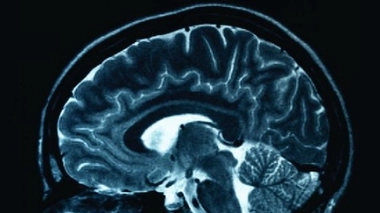

• Cerveau et neurologie

Cerveau et neurologie